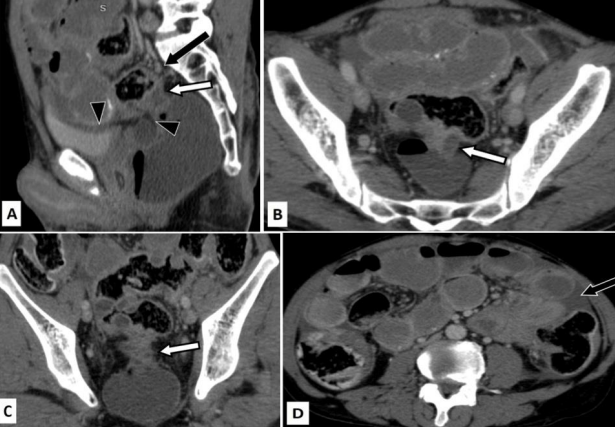

Figure 3: True positive for T4 disease and false positive for nodal involvement.

Case of 45 years old male who presented to the emergency room with pain in abdomen and distension.

Figure 3A (axial) and 3B (sagittal) CT images in venous phase show a relatively well-defined cavitating mass (white arrow) arising from the sigmoid colon. Fistulous communication with anterior ileal loops can be seen (black arrow).

Figure 3C (axial CT image in venous phase) shows multiple dilated small bowel loops with air fluid levels suggestive of obstruction. Arrowhead points to an enlarged para-aortic lymph node with calcification. Figure 3D (axial CT image in venous phase) shows diffuse fatty liver with multiple small sub centimetric hypo enhancing nodules suggestive of micrometastasis. A larger hypo enhancing lesion was seen in the left lobe(arrow).  Palliative surgery was performed and the post-operative histopathology revealed T4 disease of the primary tumor. The para-aortic node was negative for malignancy.

Figure 4: False negative for T4 disease and true positive for nodal negative disease (N0).

Case of 70 years old female with abdominal pain and loss of appetite. She underwent an ultrasoud which showed rectal wall thickening. Colonoscopy was done subsequently which revealed ulcerative growth in the recto-sigmoid junction. Biopsy was taken during colonoscopy which came out to be positive for malignancy (adenocarcinoma).

Figure 4A (Sagittal CT image in venous phase) shows severe apple-core type of wall thickening involving the rectum (white arrow). There is only minimal pericolic fat edema. Extramural vascular invasion is seen (black arrow). The fat planes with urinary bladder and seminal vesicles are maintained (black arrowheads)

Figure 4B (axial CT image in venous phase) shows severe apple-core type of wall thickening (arrow). Figure 4C (Coronal CT image in venous phase) shows the thickening with only minimal pericolic fat stranding (arrow). Figure 4D (Axial CT image in venous phase) shows multiple dilated small bowel loops with air-fluid levels suggestive of bowel obstruction. Minimal ascites is present (arrow).